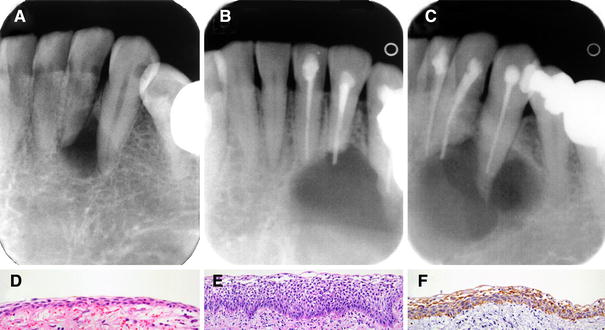

Unicystic Ameloblastoma

A 30-year-old man was referred for evaluation of a small, interradicular radiolucency between the lateral incisor and canine of the left mandible (Fig. 1a). Six years postoperatively, the patient returned with a large multilocular radiolucency causing root resorption (Fig. 1b, c). Microscopic findings of the primary lesion, i.e., thin-walled cyst lined by flattened, non-keratinizing squamous epithelium, were compatible with the clinically presumed diagnosis of lateral periodontal cyst (Fig. 1d). The recurrent cyst however revealed features diagnostic of unicystic ameloblastoma, luminal type (Fig. 1e). By immunohistochemistry, focal but intense reactivity for calretinin was evident in the lining epithelium (Fig. 1f). The patient is free from recurrence 8 years after marginal resection.

Fig. 1

Unicystic ameloblastoma. a Periapical radiograph at time of first surgery, b and c six-year postoperative periapical radiographs, d primary cyst lined with thin, non-keratinizing squamous epithelium, e ameloblastoma lining of recurrent cyst (Hematoxylin–Eosin—d ×400, e ×200), f calretinin expression (ABC method, ×200)